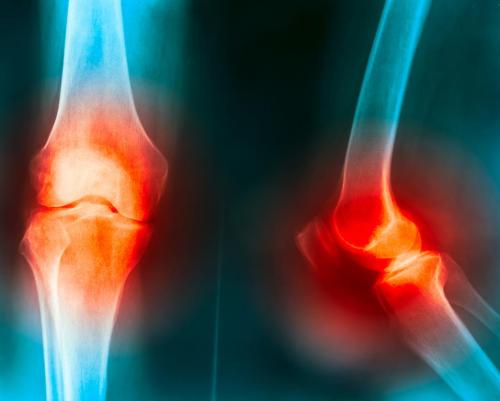

骨關節(jié)炎治療現(xiàn)狀

骨關節(jié)炎主要發(fā)生在中老年和關節(jié)負荷較大的運動員,累及負重滑膜關節(jié),引起關節(jié)疼痛及功能障礙。病理變化主要包括關節(jié)軟骨破壞,軟骨下骨硬化和滑膜增生。關節(jié)軟骨是覆蓋于關節(jié)表面,含較少細胞成分、致密膠原及糖蛋白基質構成的一層光滑結締組織,其內不含血管、淋巴管等結構一。關節(jié)軟骨一旦受損,因缺乏血供及營養(yǎng)供給受限,自身修復與再生能力有限。